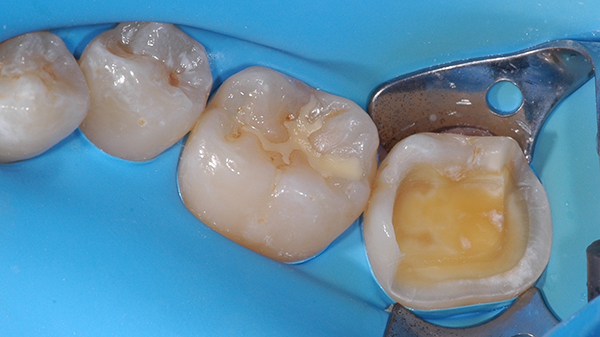

E' proposto alla paziente il piano di trattamento descritto e nel secondo appuntamento si è provveduto, previa anestesia tronculare del ramo mandibolare di destra, all'isolamento del campo operatorio mediante posizionamento della diga di gomma.

Si è proceduto attraverso frese diamantate sferiche e cilindriche ad alto-medio grit ( 107- 151 µm) montate su moltiplicatore di giri a rimuovere tutto lo smalto affetto da amelogenesi imperfetta e esporre il tessuto dentale normale.

Alla fine della procedura di preparazione dentale la cavità evidenzia ampie aree di dentina esposta ma altresì un contorno ben rappresentato di smalto sano e normale suscettibile al trattamento con procedure adesive smalto-dentinali.

Le procedure cliniche sono state indirizzate a isolare l'organo pulpo-dentinale mediante la messa in opera del sigillo immediato della dentina esposta "immediate dentin saling" ( 2 ) utilizzando allo scopo un sistema adesivo mild self-etch a due passaggi al quale ha fatto seguito foto polimerizzazione dello stesso secondo le indicazioni fornite dal fabbricante.

La rilevazione dell'impronta della cavità e dell'arcata dentaria è condotta mediante polietere da impronta e la cavità preparata ha subito temporizzazione per mezzo di materiale da otturazione provvisoria a base resinosa.